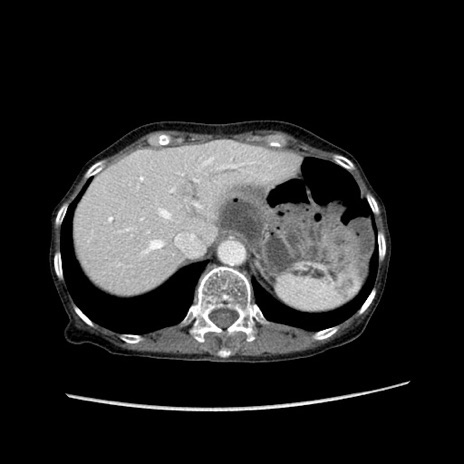

症例25(横断像)

【症例】80歳代女性

【主訴】胸のつかえ感

【現病歴】約9時間前に食後から胸のつかえた感じあり、嘔吐あり、来院。

【既往歴】胃癌(全摘)、胆摘、虫垂炎

【身体所見】心窩部に圧痛あり、反跳痛なし。

【データ】WBC 5700、CRP 0.05